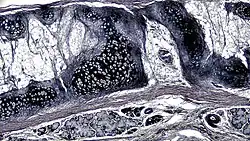

![]() A cross section of mammalian elastic cartilage | |

Elastic cartilage, fibroelastic cartilage or yellow fibrocartilage [1] is a type of cartilage present in the pinnae (auricles) of the ear giving it shape,[2] provides shape for the lateral region of the external auditory meatus,[3] medial part of the auditory canal[3] Eustachian tube, corniculate and cuneiform laryneal cartilages,[3] and the epiglottis. It contains elastic fiber networks and collagen type II fibers.[4] The principal protein is elastin.

Elastic cartilage is histologically similar to hyaline cartilage but contains many yellow elastic fibers lying in a solid matrix. These fibers form bundles that appear dark under a microscope. The elastic fibers require special staining since when it is stained using haematoxylin and eosin (H&E) stain it appears the same as hyaline cartilage.[3] Verhoeff van Geison stains are used (giving the elastic fibers a black color), but aldehyde fuchsin stains, Weigert's elastic stains, and orcein stains also work.[3] These fibers give elastic cartilage great flexibility so that it is able to withstand repeated bending. Similarly to hyaline one or multiple chondrocytes lie between the spaces (or lacunea) in the fibres.[2] The chondrocytes only make up 2% of the tissue's volume.[2] Chondrocytes and the extracellular matrix are contained in an outerlayer named the perichondrium[2] (which is a layer of dense irregular connective tissue that surrounds cartilage which is independent of the joint).[3] It is found in the epiglottis (part of the larynx), and the pinnae (the external ear flaps of many mammals). Elastin fibers stain dark purple/black with Verhoeff's stain.

The extracellular matrix contains Elastin, fibrillin, glycoproteins, collagen types II, IX, X, and XI, and the proteoglycan aggrecan.[2] the components within the extracellular matrix are produced by the chondroblasts located within the edges of the perichondrium.[2]